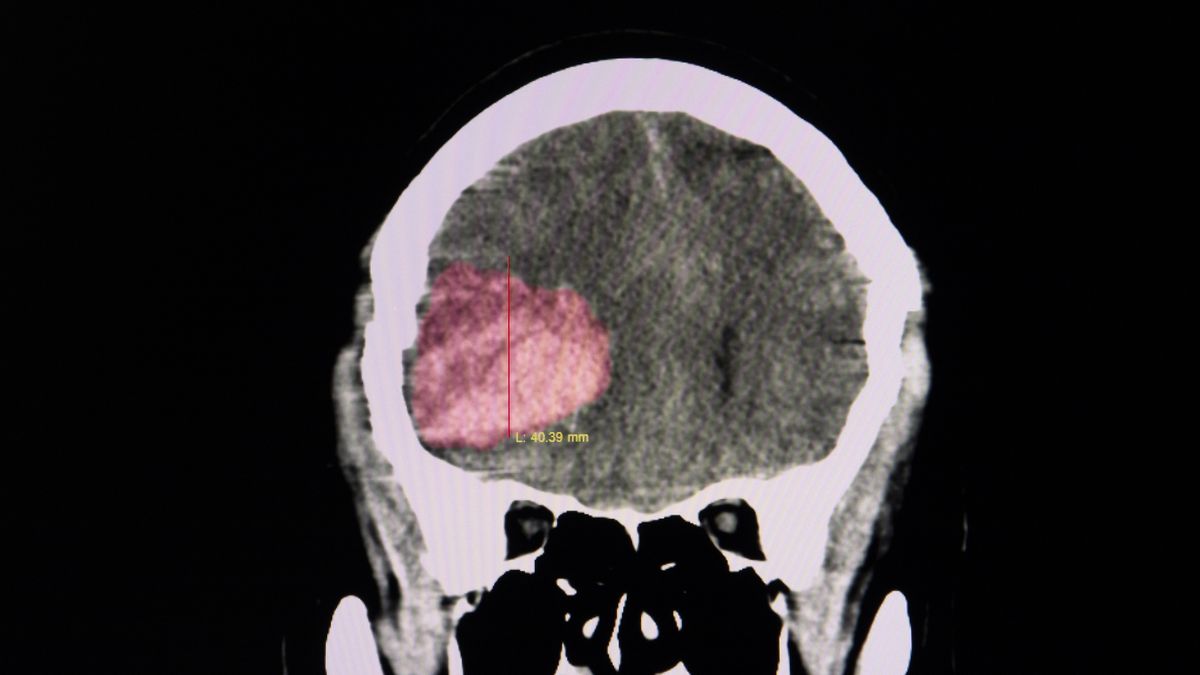

Zdjęcie mózgu pacjenta z widocznym zakrzepemZdjęcie mózgu pacjenta z widocznym zakrzepem

Źródło zdjęć: © Getty Images | Sopone Nawoot